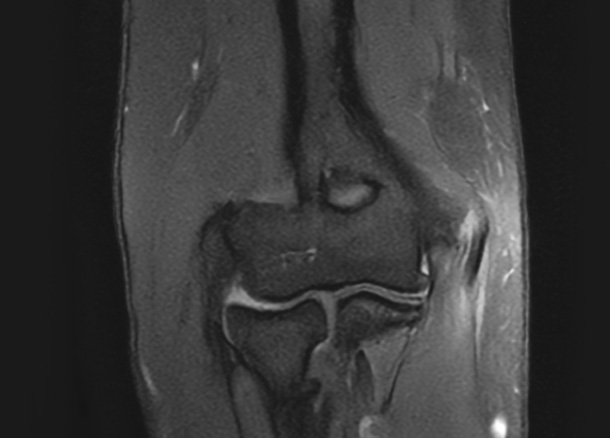

After 수술 후

1년 후 완전 정상화